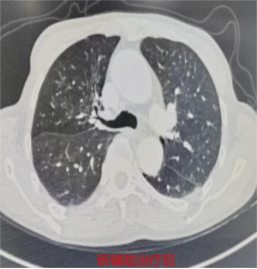

71岁的林先生(化名),4个月前在外院被确诊为右肺上叶肺门处鳞癌(IIIA期),突如其来的重病让全家陷入焦虑,辗转转诊至我院胸心外科寻求进一步治疗。我院胸部肿瘤多学科团队(MDT)首席专家、胸心外科主任医师何昌进牵头,对林先生的病情进行全面研判,结合其高龄、身体基础状况及肿瘤分期,为其量身制定了新辅助治疗联合手术的个体化方案。经过4个周期的新辅助治疗,林先生复查结果显示,肿瘤显著缩小,顺利达到手术指征,为后续手术治疗奠定了坚实基础。

3月10日,胸心外科副主任医师颜海强带领团队为林先生实施了胸腔镜下右肺上叶切除+支气管成形+肺门纵隔淋巴清扫术。术中探查发现,肿瘤紧邻支气管开口,且经新辅助治疗后,肿瘤区域纤维化严重,血管与支气管致密粘连,解剖结构复杂,手术难度极高、风险不小。手术团队沉着应对,凭借精湛的微创操作技巧,精细分离粘连组织,精准辨识并保护重要血管、神经,最终成功将肿瘤完整切除,术中冰冻病理提示支气管残端阴性,确保了手术的根治效果。

术后,在医护团队的精心护理下,林先生恢复良好,无明显并发症,术后病理结果显示肿瘤降期至IIB期,达到理想治疗效果,已顺利康复出院。